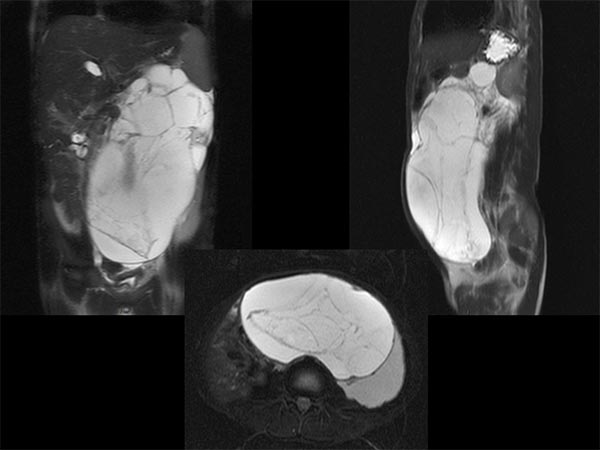

The first case is a 5-year-old girl with distended abdomen. On coronal and transverse T2-weighted, fat-suppressed MRI, an extensive macrocystic lymphatic malformation is visible with large cysts displacing the bowel.

Fat-saturated, T2-weighted MRI in three planes reveals the cause: retroperitoneally located giant cysts due to a macrocystic lymphatic malformation.